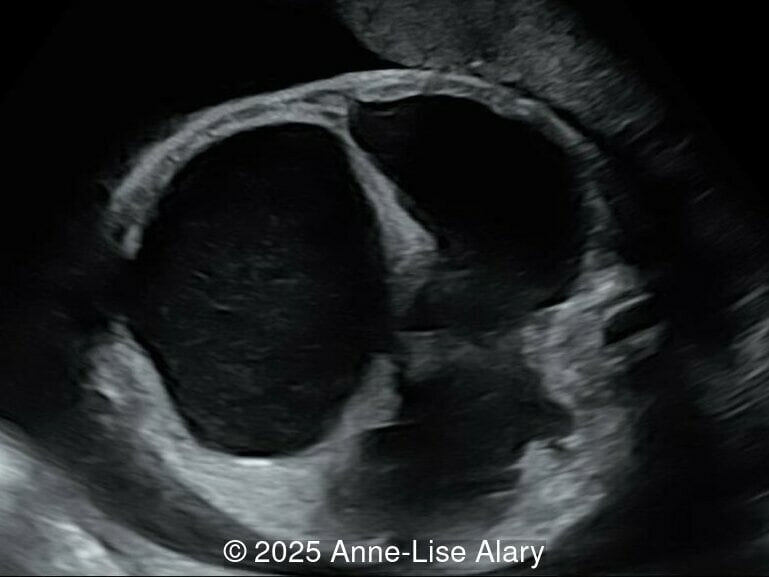

Our prenatal ultrasound revealed a male fetus with megabladder, dilation of both ureter and kidneys, and thinned kidney parenchyma consistent with Lower Urinary Tract Obstruction (LUTO). Additional findings suspected on ultrasound and confirmed on computed tomography included:

The diagnosis of PBS is often made in the second trimester of pregnancy, although it has been described as early as 11 weeks of gestation [20]. The most frequent ultrasound findings are a large, thin-walled bladder accompanied by bilateral hydroureter/hydronephrosis, dysplastic kidneys with echogenic renal parenchyma and renal cortical cysts, and abdominal wall laxity which is better viewed after bladder decompression [21]. Cryptorchidism can be detected prenatally by 28 to 30 weeks gestation when the testes descend into scrotum. There may be a patent urachus, visible as a cystic connection between bladder and umbilicus. Oligohydramnios is a frequent finding, which makes it difficult to visualize the associated anomalies.